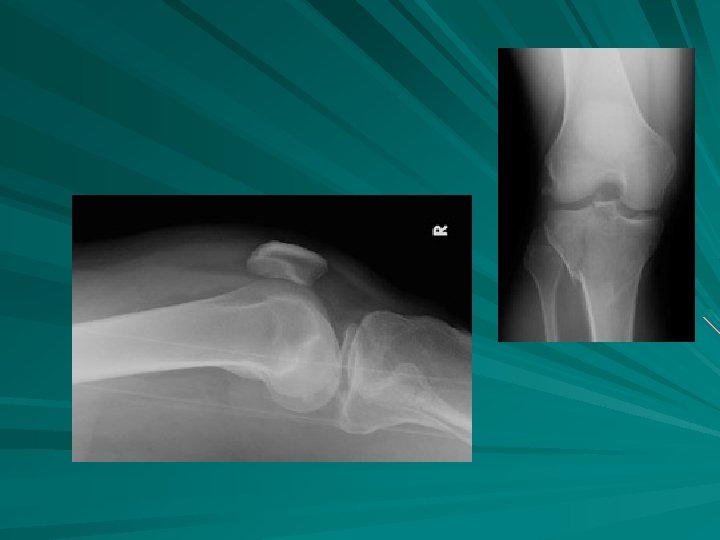

FX RADIAL HEAD

greenstick

comminuted Open fracture